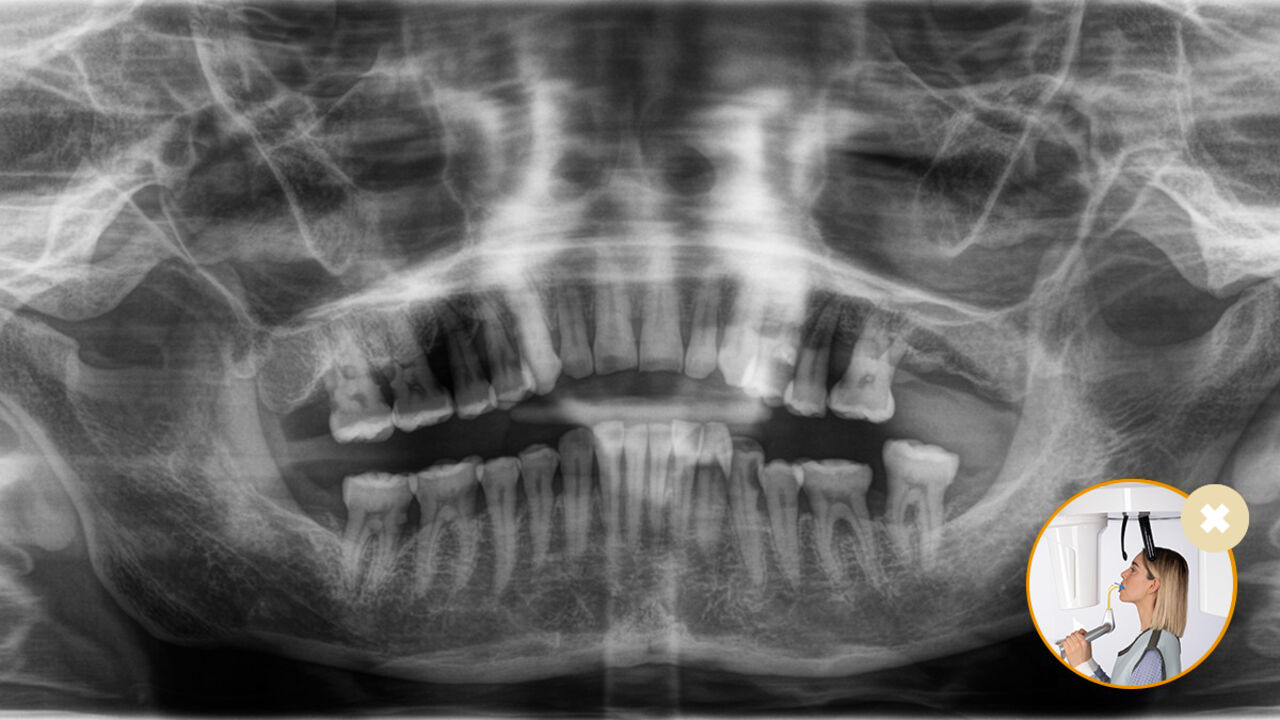

Relaxed and pleasant procedures are equally important for everyone, the patients and the staff alike. It is satisfying and motivating when everything goes according to plan and things go smoothly. The use of Orthophos or Axeos with Sidexis 4 provides you with targeted support. The X-ray systems are simple to use, yet unique in their diagnosis possibilities.. This ensures that every aspect of the treatment process creates a positive experience.

Correct patient positioning leads to high image quality to support an accurate diagnosis and facilitates and improves patient experience.